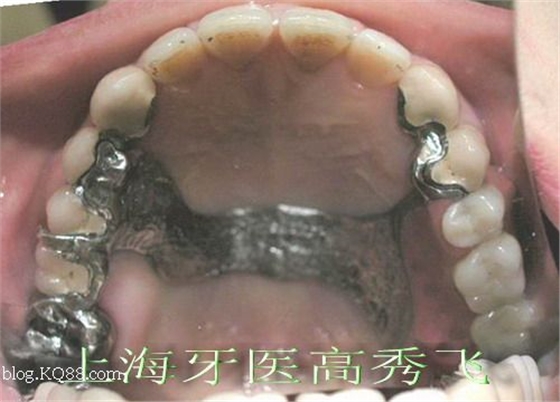

修復(fù)設(shè)計(jì):13、14為附著體基牙,烤瓷冠修復(fù),遠(yuǎn)中放置三段可調(diào)式附著體,考慮到對側(cè)牙齒無齲壞,設(shè)計(jì)25、26雙臂卡,上頜后腭板鈷鉻合金支架義齒。牙齒制備后合面觀:

附著體戴入后合面觀: